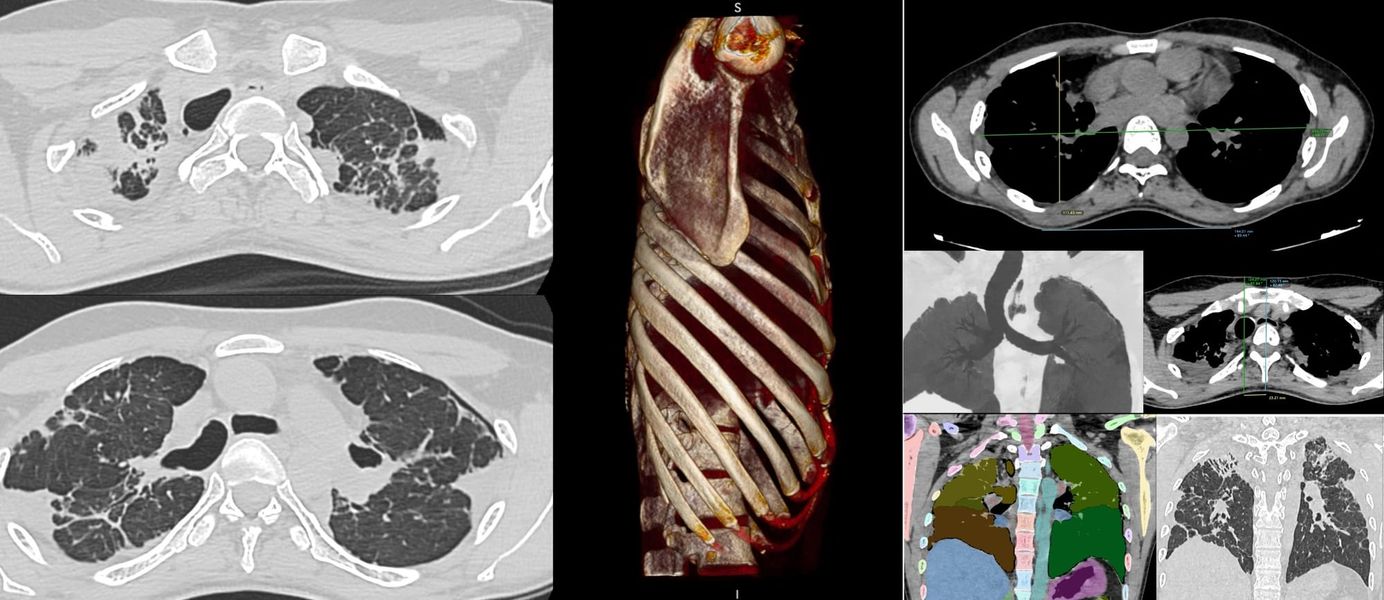

The PDIF sign is basically the presence of a fibrosing ILD typically compacted within the last 2 cm of the peridiaphragmatic lung and may suggest not just CTD-ILD but specifically myositis ILD